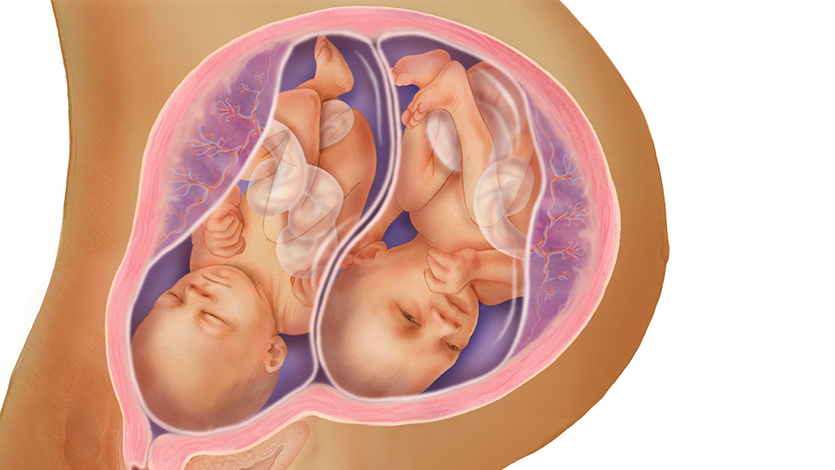

قیمت: 68٬000 تومان - دسته بندی فایل: پاورپوینتپاورپوینت حاملگی چند قلویی

فروش ویژه پاورپوینت حرفه ای حاملگی چند قلویی با تخفیف استثنایی فقط 72 هزار تومان تعداد اسلاید : 39 اسلاید